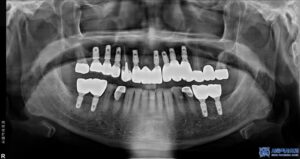

치료 후 2개월이 지나고 임플란트가 잇몸과

뼈에 잘 자리 잡았는지 확인한 뒤

최종 보철물을 세팅하는

단계로 넘어갔는데요.

치료 마무리 후 사진입니다.

환자분께서도 최종 보철물을 장착한 후

너무 자연스럽고 불편한 곳도 없다며

매우 만족스러워 하셨습니다.